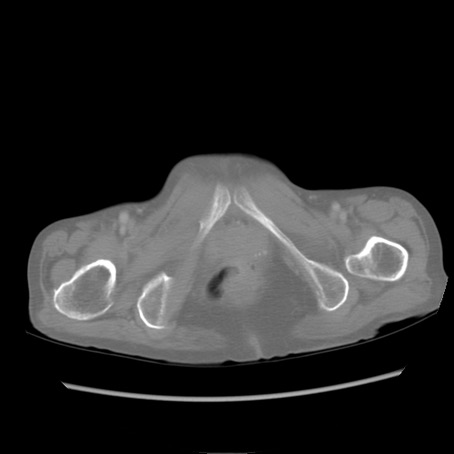

症例25(横断像)

【症例】80歳代女性

【主訴】胸のつかえ感

【現病歴】約9時間前に食後から胸のつかえた感じあり、嘔吐あり、来院。

【既往歴】胃癌(全摘)、胆摘、虫垂炎

【身体所見】心窩部に圧痛あり、反跳痛なし。

【データ】WBC 5700、CRP 0.05